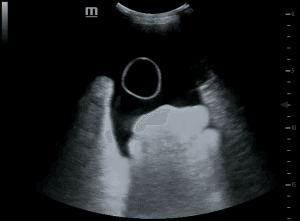

A 32-year-old man presented to the emergency department with a two-day history of acute onset of swelling and pain in the left calf. The patient had a history of hepatitis C, intravenous drug use with past admissions due to repeated soft-tissue abscesses at drug injection sites. The patient denied any trauma to the leg, and was not on any regular medication. On examination, there was marked swelling and tenderness in the left calf. He had a temperature of 37.7°C, a heart rate of 110 beats/min, a blood pressure of 110/707 mm Hg, and a respiratory rate of 18 breaths/min.  A three-point compression point-of-care-ultrasound (POCUS) of the leg was performed which did not show any evidence of a DVT; however, a large cystic structure in the posterior aspect of the calf was identified (Figure 1). A knee ultrasound also demonstrated a fluid-filled area suggesting an associated knee effusion. A knee aspiration revealed a WBC count of 135 000 cells/µL, with 95% neutrophils (Figure 2). The patient was admitted under Orthopaedics with a suspected diagnosis of a septic knee and a ruptured infected Baker’s cyst. Blood test results at admission are shown in supplementary material (online Table S1). An inpatient Doppler ultrasound of the leg excluded DVT. A musculoskeletal ultrasound of the left leg confirmed the findings of an extremely large complex haemorrhagic or infected Baker’s cyst. The patient was initially treated with intravenous flucloxacillin. A knee aspiration culture revealed staphylococcus aureus. The patient was planned for surgical treatment however he self-discharged from hospital. The patient returned to Hospital 1 month later feeling unwell, pyrexial and complaining of pain in the right sternoclavicular area. Computerized tomography (CT) of the chest demonstrated acute septic arthritis of the right sternoclavicular joint with superficial phlegmon and small superficial ring enhancing collection anterior to the medial right clavicle and superiorly, appearances most likely secondary to Staphylococcus aureus. The knee swelling had improved, but symptoms were still persistent, however the patient refused any invasive treatment and accepted an intravenous course of Vancomycin.

Figure 1. Within the posterior aspect of the left calf on the medial aspect there is an extremely large cystic lesion measuring 18.7 cm in length and 4 cm in width with no adverse features.  The cystic lesion is communicating with the semimembranosus/medial head gastrocnemius bursa more proximally in the knee where it demonstrates internal echoes and synovial thickening and a single septation.